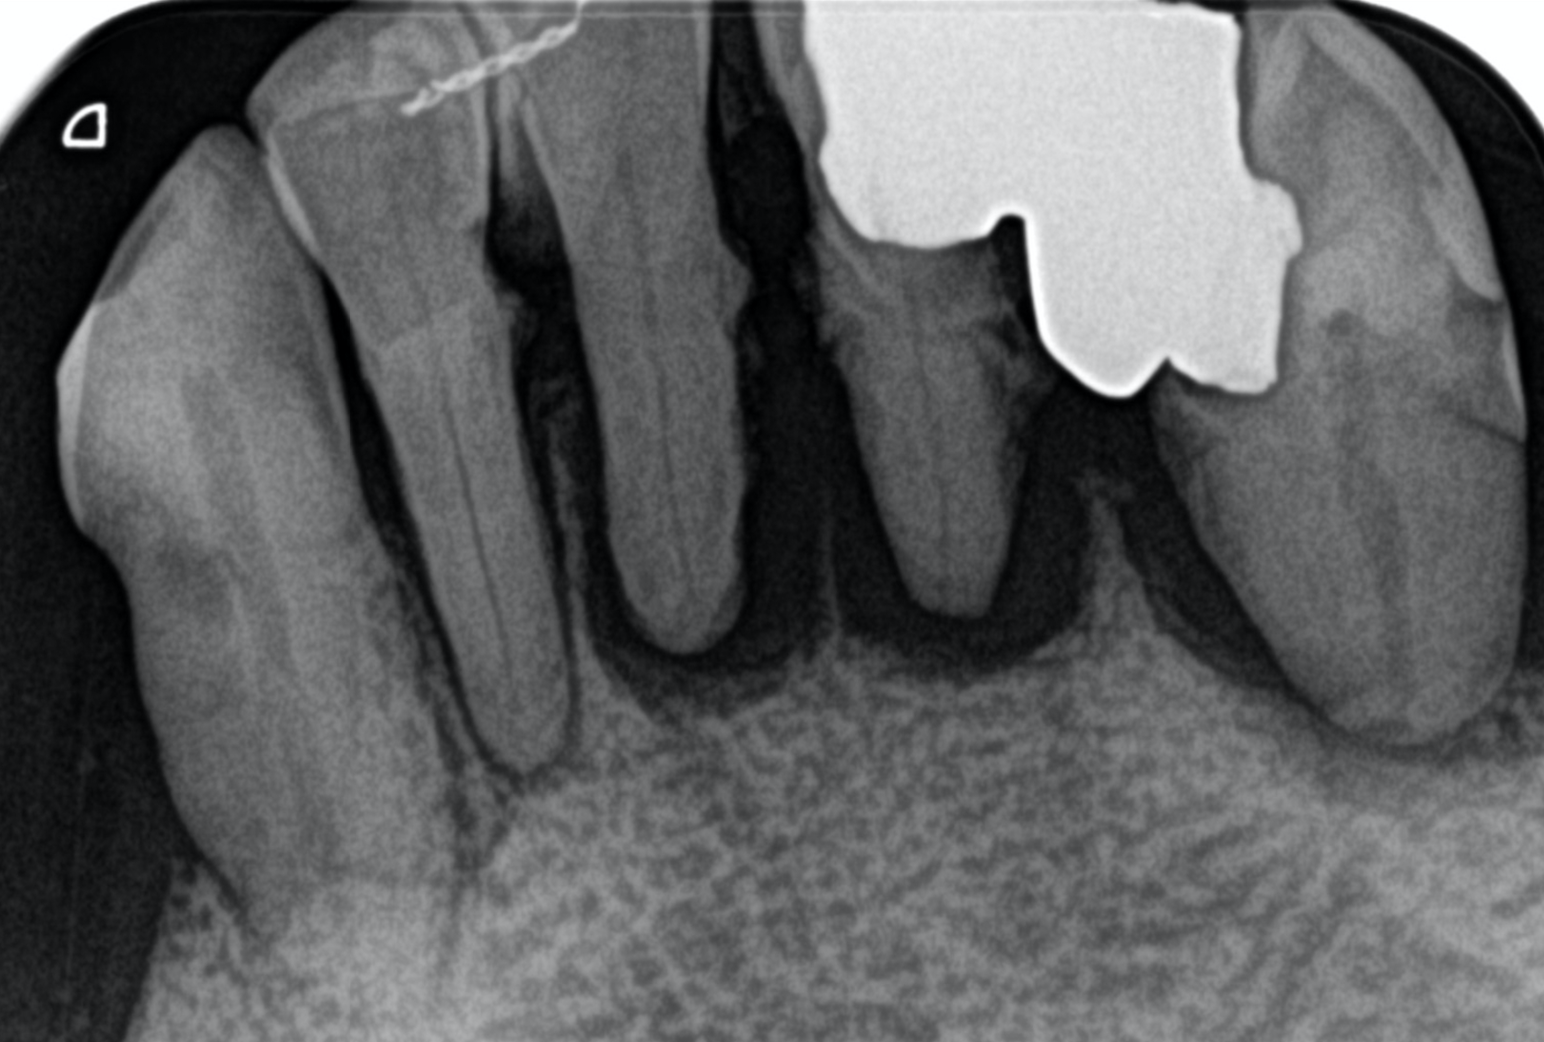

人間の歯には根っこがあり、その根っこが硬い顎の骨に埋まっています。

そのため硬いものを食べたりしても歯はビクともしません👄

しかし、歯磨きが不十分だったり、定期的に歯科医院でのケアをしていないと、お口の中の汚れである歯垢(プラーク)や歯石がどんどん溜まって、その中に住み着いている細菌が顎の骨を溶かしてしまいます…。

支えとなっていた顎の骨が溶けると歯はグラグラになり、最終的には抜けてしまいます😱

これが歯周病です。